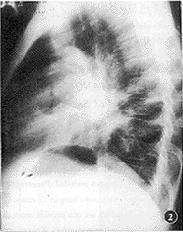

图2 胸部侧位片(与图1同一病例)示肿块位于肺门前方,呈囊状,其内可见软组织结节,手术病理为囊性畸胎瘤

另3例破入肺内者,X线表现既有纵隔肿块,亦有肺内肿块。肺内肿块边缘模糊或部分边缘清楚,其中1例体层示分叶状厚壁空洞,其内可见类圆形软组织结节(图3),另2例为实性。